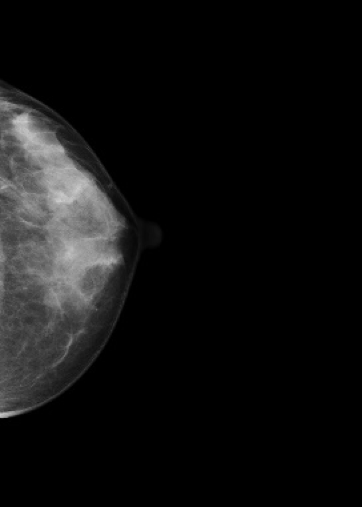

マンモグラフィ検査

装置の紹介

当院では2016年5月に乳房撮影装置

MAMMOREX Pe・ru・ru DIGITAL

(キヤノンメディカルシステムズ)を導入しました。

FPDを搭載した装置で、解像力やコントラストが向上し微細な石灰化や腫瘤をより鮮明に描出することが可能です。検査は健診棟の女性専用エリア内に併設されたマンモグラフィ専用の検査室で行っており、安心して検査を受けていただけます。撮影はNPO法人日本乳がん検診精度管理中央機構の認定を受けた女性技師が担当します。

マンモグラフィとは

専用の装置を用いて行う乳房のX線撮影のことです。 マンモグラフィは視触診では分からない早期乳癌の微細な石灰化や、触っても分からない小さなしこりの描出に優れています。

*当院では左右の乳房それぞれで2方向の撮影(CC撮影・MLO撮影)を計4枚行います。

*2方向から撮影を行うことで乳房全体をまんべんなく写すことができます。

圧迫の必要性

厚みのある乳房の中にはたくさんの乳腺や脂肪などが重なって存在しています。

これらを均等に伸ばし組織同士の重なりを分離することで、小さなしこりや石灰化の粒をより見つけやすい画像にすることができます。

*実際に乳房を圧迫する時間は1枚の撮影で数十秒程度です。

画像1枚目:圧迫なし、画像2枚目:圧迫あり